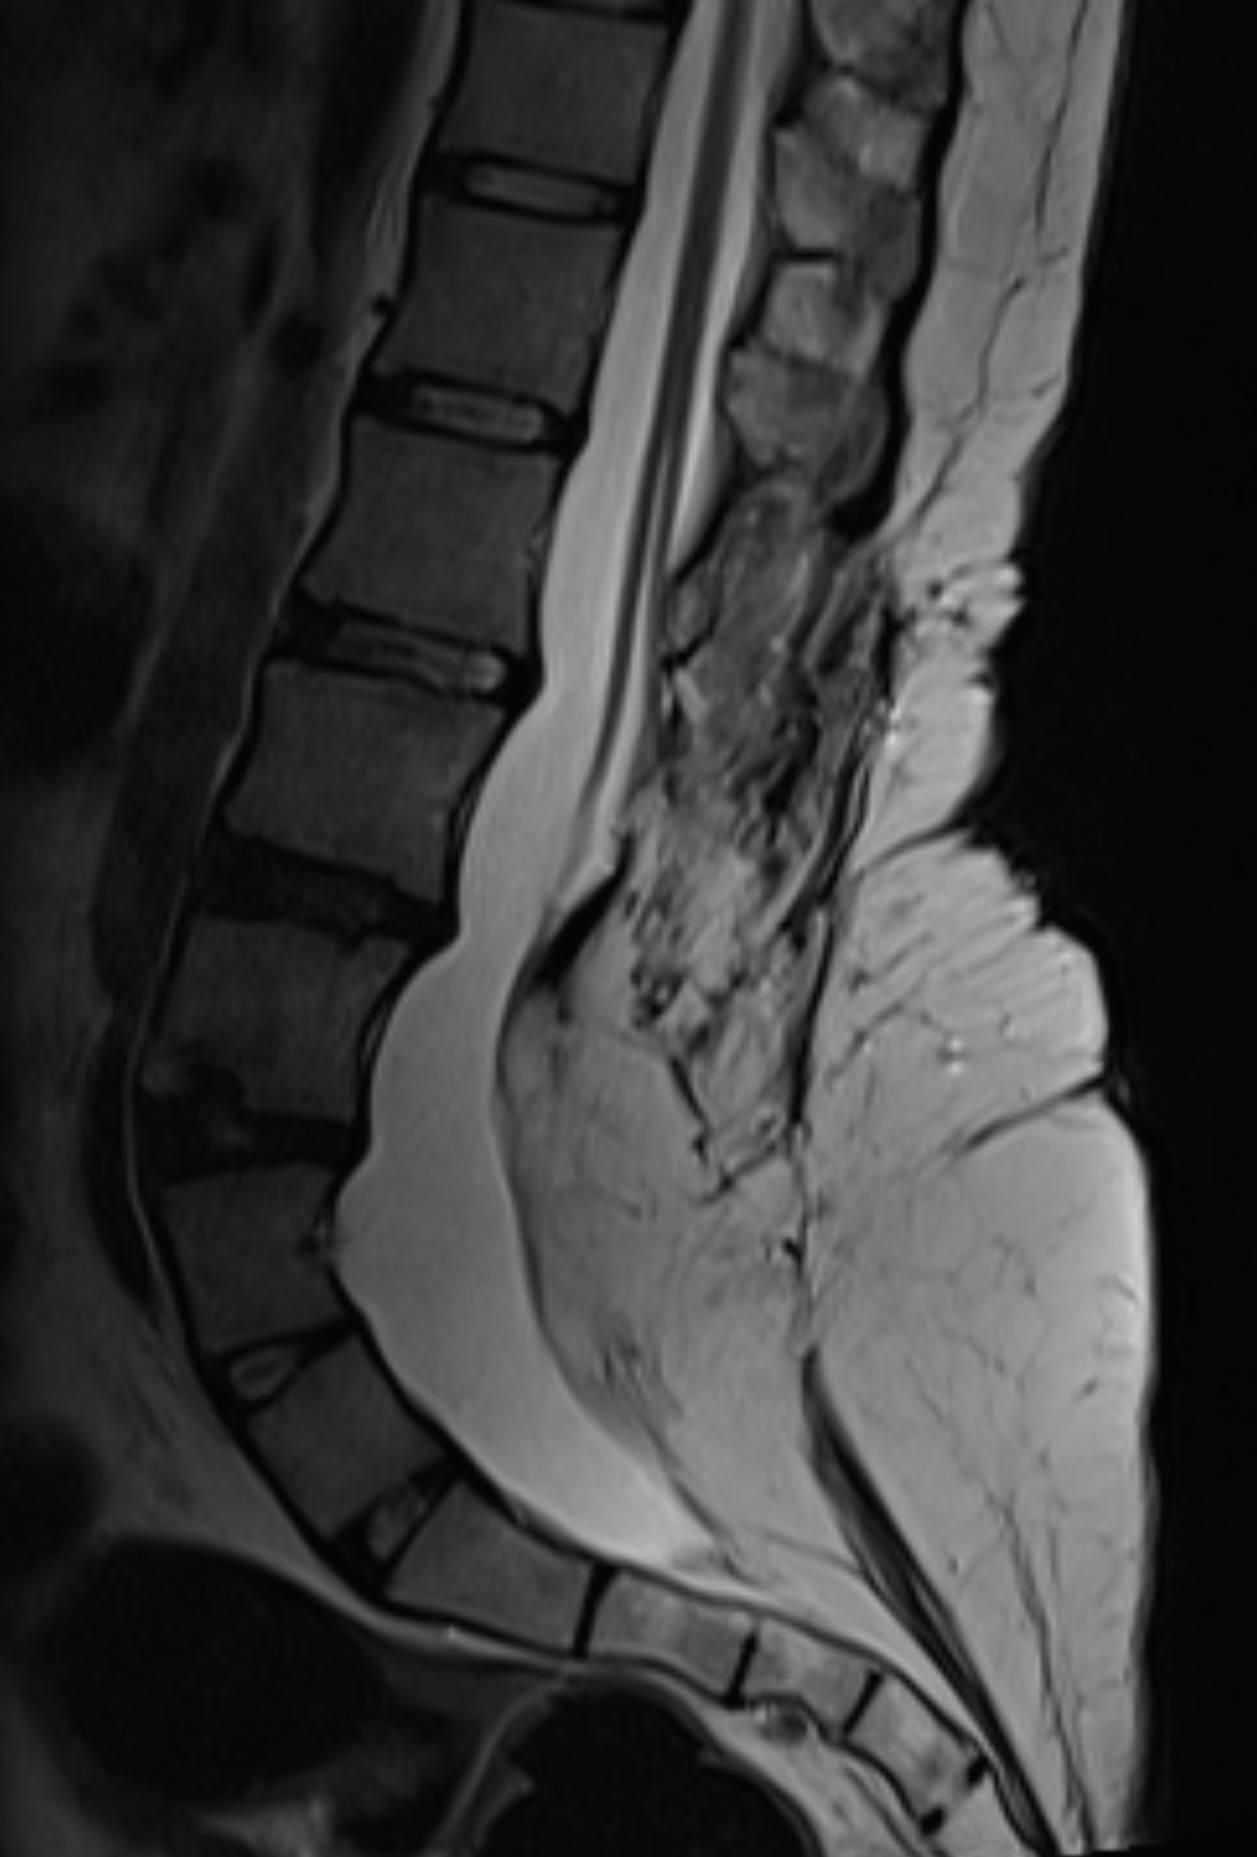

Естественное течение аномалий развития спинного мозга с известным неблагоприятным безоперационным прогнозом в настоящее время встречается редко, поскольку в большинстве случаев хирургическое лечение проводится в раннем возрасте, а длительное наблюдение за такими пациентами в целом считается неэтичным, за исключением единичных случаев и некоторых форм порока. Тем более ценно данное клиническое наблюдение.

При рождении у ребенка выявлено подкожное образование в поясничной области, девочка наблюдалась по месту жительства у детского хирурга, невролога, ортопеда, до года осмотрена нейрохирургом, выявлен легкий нижний вялый парез (мышечная слабость) справа. По данным МРТ диагностирован порок развития - липомиеломенингоцеле, фиксированный спинной мозг.

В дальнейшем наблюдалась ортопедом с диагнозом сколиоз I-ІІ ст., в возрасте 5 лет впервые выявлено нарушение функции тазовых органов - гиперрефлекторный мочевой пузырь, с возраста 13 лет отмечено укорочение правой нижней конечности до 1см, болевой синдром, периодическое (стрессовое) недержание мочи.

В динамике формирование походки с анталгической установкой, прихрамывание, степпинг, при осмотре неврологом ахилловы рефлексы отсутствуют, сила в ногах снижена до 3 баллов дистально, поверхностная чувствительность снижена до анестезии по типу низких носков с двух сторон, паралитическая эквино-варусная деформация обеих стоп.

К возрасту 17 лет выраженные боли в спине и ногах (больше в правой), укорочение правой нижней конечности на 2 см, гипотрофия мышц правого бедра и правой голени - минус 2см, разгибательная контрактура обоих голеностопных суставов и левого коленного сустава2 ст., частые мочеиспускания, периодическое дневное недержание мочи, слабость в ногах, выраженное нарушение походки.

Причина столь длительного течения заболевания в данном случае заключается, со слов мамы ребенка, в опасениях, вызванных как неубедительными доводами в пользу операции со стороны специалистов по месту жительства, так и ложными страхами, внушаемыми, со стороны родителей других пациентов (зачастую с абсолютно другими диагнозами) из «родительских чатов»: не будет ходить, станут «резать» каждый год и т.д.

Операция по освобождению спинного мозга из рубцовой и жировой ткани длилась 6 часов, цели вмешательства были достигнуты, девочка выписана на 7е сутки без ухудшения состояния и с надеждой на то, что удалось остановить прогрессирование заболевания. При этом очевидно, что в результате длительной фиксации и натяжения спинного мозга, большая часть проблем, в первую очередь ортопедических, к сожалению, уже не разрешится…